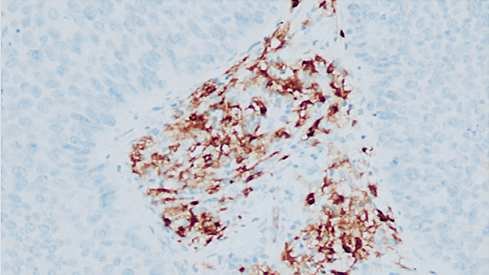

一、检测背景随着全球首款靶向Claudin18.2(CLDN18.2)的抗体药物佐妥昔单抗在国内外上市,胃癌治疗进入精准靶向新时代。中国临床肿瘤学会(ChineseSocietyofClinicalOncology,CSCO)、美国国立综合癌症网络(NationalComprehensiveCancerNetwork,NCCN)、欧洲肿瘤内科学会(EuropeanSocietyofMedicalOncology,ESMO)等权威指南以及《胃癌Claudin18.2临床检测专家共识(2025版)》均推荐对胃/胃食管交界处(Gastroesophagealjunction,GEJ)腺癌进行CLDN18.2检测,为精准筛选靶向治疗获益人群提供关键依据,为晚期胃癌患者带来新的生存希望[1-3]。研究证实约40%的胃/GEJ腺癌患者为CLDN18.2阳性表达,提示这部分患者可能从靶向治疗中获益,其中接受佐妥昔单抗联合化疗方案的患者,疾病进展或死亡风险降低25%至31%,显著延长无进展生存期和总生存期。在胃癌的临床实践中,CLDN18.2免疫组织化学(immunohistochemistry,IHC)检测已成为评估抗CLDN18.2靶向治疗适用性的重要手段。二、适用人群(主要包括但不限于)初治晚期胃/胃食管交界处腺癌患者;HER2阴性寻求新靶向治疗机会者;传统治疗效果不佳的难治性患者。三、技术保障检测抗体:Claudin18.2(43-14A)。检测平台:Ventana全自动免疫组化仪。判读标准:严格按照《胃癌Claudin18.2临床检测专家共识(2025版)》强推荐的判读标准,将≥75%的肿瘤细胞具有2+/3+强度膜染色判读为阳性/高表达,并出具明确的阳性/阴性及具体表达水平的报告,如“Claudin18.2阳性(3+,90%)”、“Claudin18.2阴性(2+,30%)”等。四、检测结果判读示例图①-④胃腺癌肿瘤细胞及周围正常黏膜腺体Claudin18.2的表达情况①非肿瘤性胃黏膜腺体(右半部分)为细胞膜强阳性着色,肿瘤细胞(左半部分)呈2+细胞膜环形阳性着色;②非肿瘤性胃黏膜腺体(右半部分)为细胞膜强阳性着色,肿瘤细胞(左半部分)呈2+细胞膜基底外侧/外侧阳性着色;③、④肿瘤细胞呈3+细胞膜环形阳性着色参考文献:《胃癌Claudin18.2临床检测专家共识(2025版)》专家委员会.胃癌Claudin18.2临床检测专家共识(2025版)[J].中华病理学杂志,2025;54(7):718-725.doi:10.3760/cma.j.cn112151-20250408-00245.ShitaraK,LordickF,BangYJ,etal.ZolbetuximabplusmFOLFOX6inpatientswithCLDN18.2-positive,HER2-negative,untreated,locallyadvancedunresectablemetastaticgastricgastro-oesophagealjunctionadenocarcinoma(SPOTLIGHT):amulticentre,randomised,double-blind,phase3trial.Lancet,2023;402(10398):1655-1668.PMID:37068504.doi:10.1016/S0140-6736(23)00620-7.ShahMA,ShitaraK,AjaniJA,etal.ZolbetuximabplusCAPOXinCLDN18.2-positivegastricgastroesophagealjunctionadenocarcinoma:therandomized,phase3GLOWtrial.NatMed,2023;29(8):2133-2141.PMID:37524953.doi:10.1038/s41591-023-02465-7.备注:本文在成稿后经由元宝大语言模型进行语言润色与逻辑优化,旨在提升表达的准确性与流畅性,核心观点与内容均由作者独立完成。‌‌